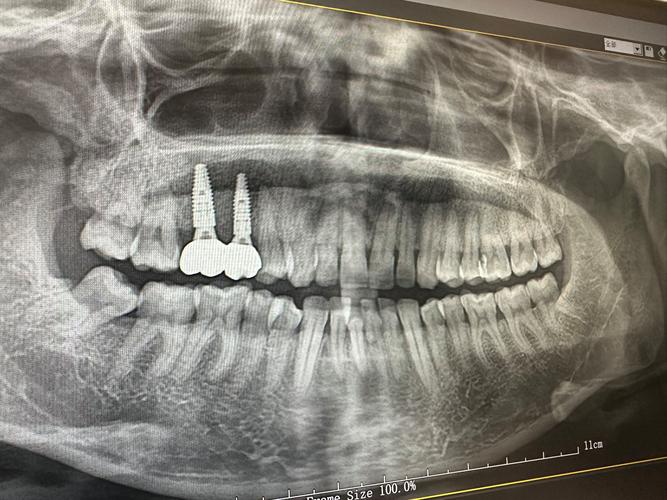

- 影像学检查(X光片): 这是评估种植体长期健康最核心的手段! 通过X光片,医生可以:

- 观察种植体周围骨头的状况(有无骨吸收)。

- 检查种植体与修复体(牙冠)的连接处有无问题。

- 评估整体口腔状况。